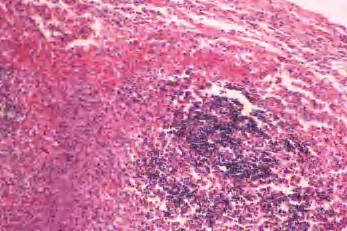

2.镜下 可见滤泡增生,生发中心扩大,含有大量核分裂像,窦组织细胞增生,窦内及实质内多数中性粒细胞浸润,可有坏死及脓肿形成。急性炎症慢性化后,则表现为滤泡、副皮质区及淋巴窦三者某一部分增生,炎细胞浸润减少并出现纤维化(图3-4、图3-5)。

图3-4 化脓性淋巴结炎

图3-5 化脓性淋巴结炎